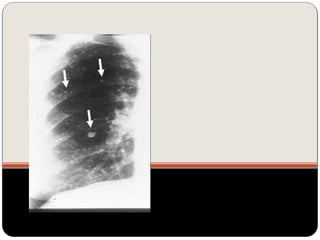

Granuloma de TB

 Nódulo sem crescimento ao longo de dois anos e com

calcificações associadas à benignidade  provavelmente

 Calcificação difusa, central ou lamelar  possível considerar

benigno;

 Causa mais comum de NPS: granuloma

(por infecção granulomatosa prévia)